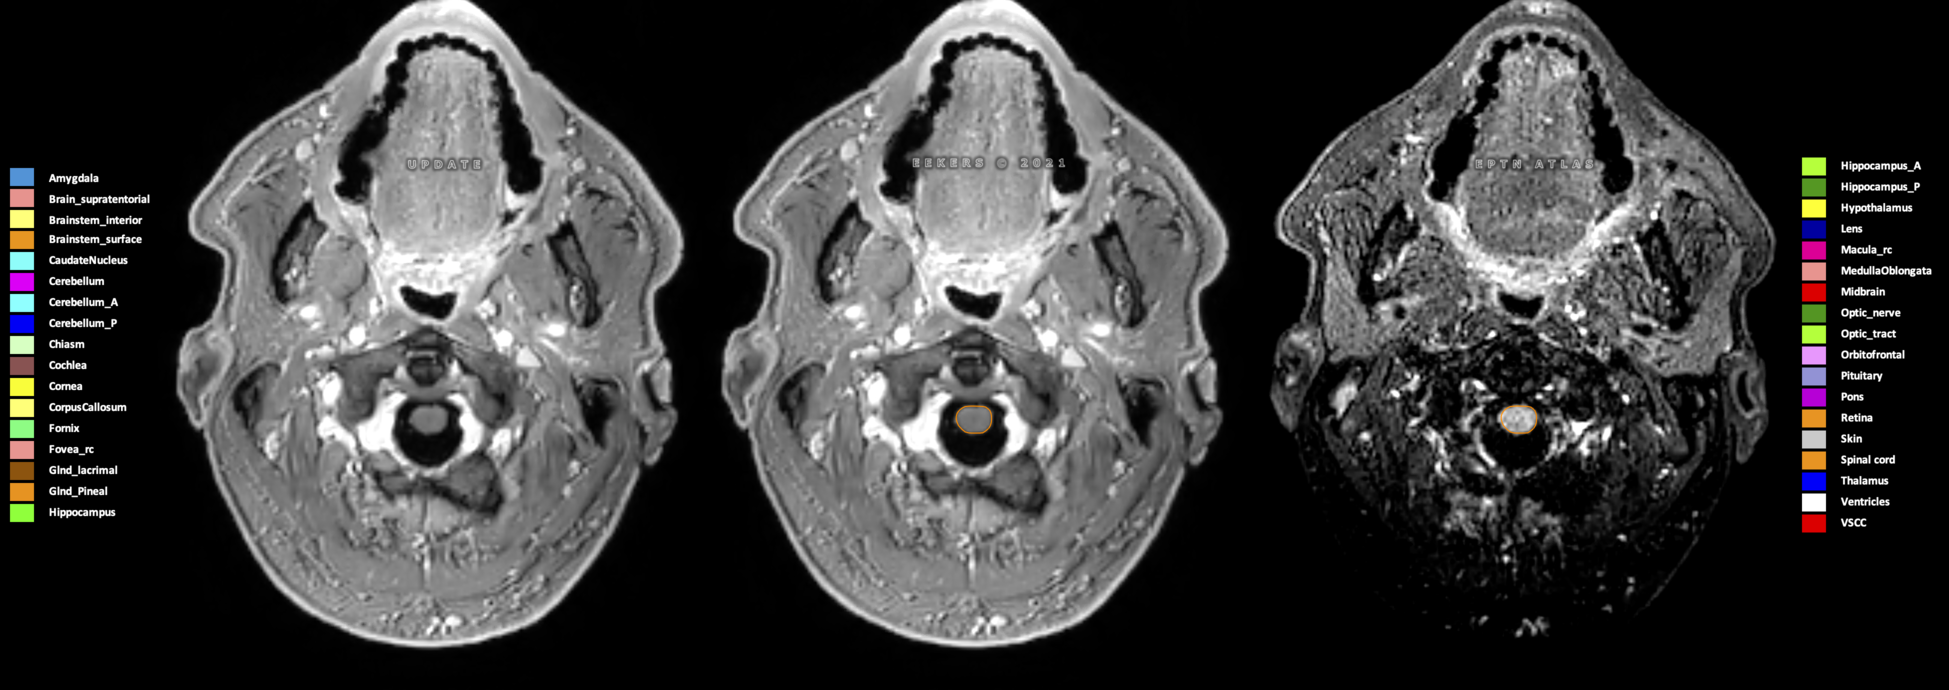

Eekers et al. have published an international neurological atlas for contouring of organs at risk in consensus with the European Particle Therapy Network (EPTN) in 2018 and an update in 2021. The purpose of this consensus atlas is to decrease inter- and intra-observer variability in delineating OARs relevant for neuro-oncology.

Included are all OARs known to be relevant for radiation-induced toxicity in neuro-oncology: brain, brainstem (midbrain, pons, medulla oblongata), chiasm, cerebellum (anterior & posterior), cochlea, cornea, hippocampus (anterior & posterior), hypothalamus, lens, lacrimal gland, optic nerve, pituitary, skin, and vestibular & semicircular canals. To further facilitate research on cognition, vision and radiological changes after irradiation of the brain, potential clinically-relevant OARs are included: amygdala, caudate nucleus, cerebellum (anterior & posterior), corpus callosum, fornix, macula, optic tract, orbitofrontal cortex, periventricular space (PVS), pineal gland, and thalamus.

Three-dimensional delineation of the 25 consensus OARs for neuro-oncology are shown on CT (WW/WL 120/40, 3000/600), 3T MR images, (T1Gd, T2FLAIR 1mm) and 7T MR (MP2RAGE 0.7 mm). All are presented in transversal, sagittal and coronal view.